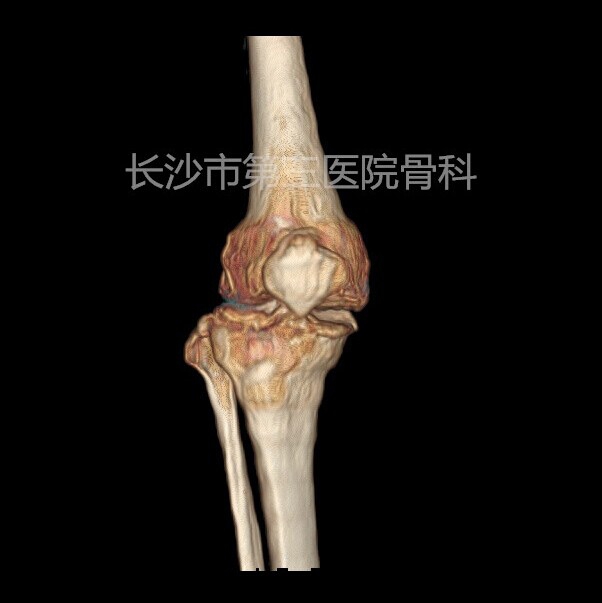

患者李某,女性,76岁。因反复右膝肿痛、活动受限10年,加重4天入院。体查:右膝内翻畸形,屈90度,伸10度,内侧关节间隙及髌骨上缘压痛,侧方应力试验阴性,肌力正常。诊断“右膝骨性关节炎”,为人工全膝关节置换适应症。

术前CT: